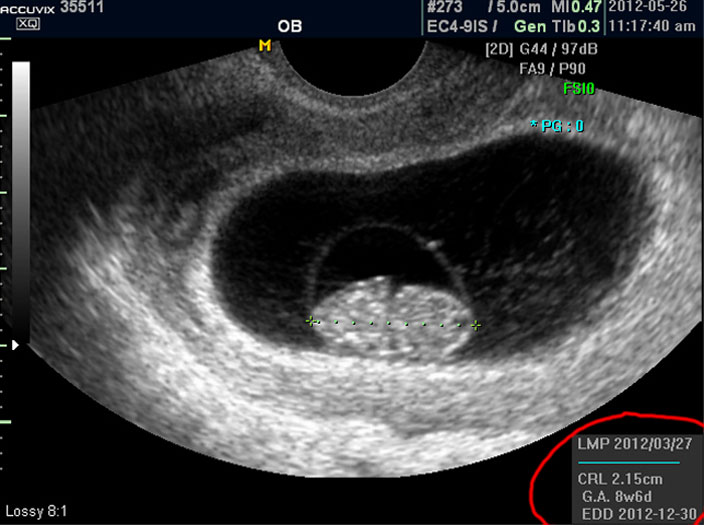

임신 8주 된 태아의 초음파 사진을 제대로 감상하는 방법을 설명드리겠습니다.

초음파 사진에서 살펴 볼 부분은 당연히 태아의 모습이겠지요.

그러나 임신 8주 정도의 초기에는 아직 아기가 쌀알 보다 조금 큰 정도이기 때문에 인간의 형체가 또렷하지는 않습니다.

그저 머리와 몸통 부분만 형성되어 있는 상태이지요.

우선 첫번째로 보이는 사진에서 가운데 하얗게 보이는 것이 태아입니다.

우측이 머리 부분이고 좌측이 몸통 부분이며 초기 임신에서는 아기 머리가 몸통의 반정도로 상당히 큰 상태입니다.

그리고 초음파 검사에서는 산전 초음파 이외의 다른 경우도 그렇지만 물에 가까운 성분일수록 검게 나오고 뼈처럼 단단해서 초음파 선이 투과하지 못하는 부분은 하얗게 나타납니다.

이는 투과 선은 다르지만 X 레이 검사 사진에서도 마찬가지입니다.

따라서 하얗게 보이는 태아 주변의 검은 부분은 양수입니다.

태아의 크기는 우측 하단에 실제 크기가 나와 있지만 아래 사진에서 빨갛게 표시한 부분의 안에 보이는 눈금이 1cm입니다.

이런 기준이나 지표들이 표시되는 것은 초음파 장비마다 조금씩 차이가 있고 위치도 다르지만 대개 비슷한 모양이라 한가지를 알면 다른 기종에서도 감상에 그리 어렵지는 않습니다.

참고로 저희는 국산 장비인 메디슨의 고급 기종인 아큐빅스라는 장비를 사용하고 있습니다.

마지막으로 볼 것은 아기의 정보를 나타내 주는 수치들입니다.

으로 우측의 LMP라고 된 숫자는 산모의 최종 월경일이며 이는 초음파로 판단한 것이 아니라 산모의 진술을 바탕으로 한 것인데 이것이 중요한 이유는 초음파는 그저 크기만을 알아 내는 것이라 임신 주수에 걸맞게 잘 자라는지 판단하려면 월경 주기를 알아야 하기 때문입니다.

그 아래 보이는 CRL이라는 것은 Crown Rump Length의 약자로 아기의 머리부터 엉덩이 끝까지의 실제 길이입니다.

임신 12주 내지 13주 정도의 초반기의 아기 발육은 주로 아기의 전체 크기를 가지고 판단하는데 엉덩이까지 체크하는 이유는 흔히 태아는 다리를 구부리고 있기 때문에 성인 인간처럼 머리끝부터 발끝까지 실제 키를 재기가 어렵기 때문입니다.

그 아래 GA 는 Gestational Age의 약자로 우리말로는 태령이라고 하며 초음파의 CRL을 기준으로 했을 때 어느 시기의 태아의 수준인가를 말해 주는 것입니다.

따라서 산모의 LMP를 기준으로 한 태령과 초음파로 측정한 태아의 태령은 1주 정도의 오차로 비슷한 것이 정상이며 간혹 최종 월경일을 틀리게 알고 있거나 아기의 발육에 문제가 있을 때는 큰 차이가 날 수 있습니다.

맨 아래의 EDD는 Estimated Due Date의 약자로 출산 예정일을 말하는데 초음파를 기준으로 했을 때 이정도 시기가 출산 예정일이 될 것이라는 계산입니다.

그러나 이것은 어디까지나 초음파로 예상한 시기이며 실제 출산은 앞뒤로 2주 씩의 오차가 있을 수 있습니다.